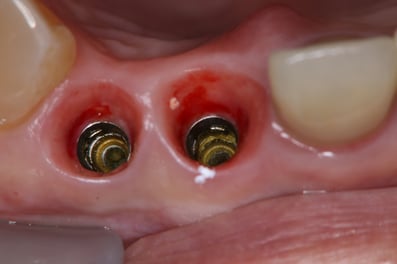

抜歯した直後にインプラントを埋入し、仮の歯を作製、唇側の骨のボリュームを保つために人工骨と結合組織を同時に移植する非常に優れた方法です。